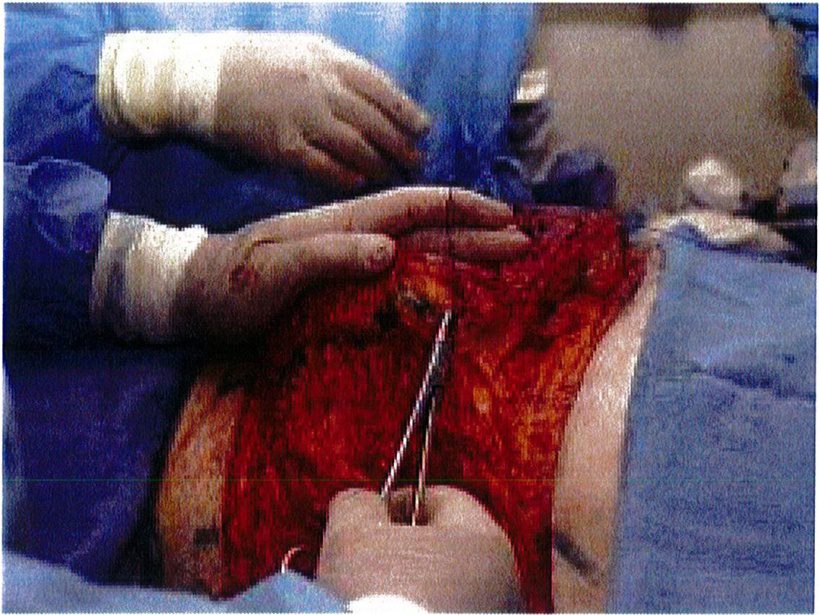

Hệ thống cân nông có thế được đánh dấu sau khi đã bộc lộ để xác định dễ dàng hơn, đồng thời các đường khâu cũng chính xác hơn. Sau đó dùng chỉ Mersilene số 1 khâu lớp cân nông lại với nhau và siết chặt chỉ để tạo thành một khối hình cầu (Hình 6). Kết quả thu được sẽ tương tự như khi bệnh nhân được đặt một khối implant cỡ lớn, với điểm hình chiếu tốt (Hình 7). Sau đó chúng được neo vào lớp cân nông phía trong (cạnh xương cùng) đã được bảo tôn trước đó. Lúc này có thể dùng chỉ Mersiline 3 (Hình 8). Cho tới nay không ghi nhận một trường hợp ứ máu hay tắc nghẽn ở tĩnh mạch vùng mô trung tâm nào.

ở hình 5) được khử biểu mô bằng dao tay hoặc dao điện để bộc lộ tới phần cân nông. Phần ranh giới của mô trung tâm này được bóc tách tới lớp cân cơ, làm chúng bị cô lập với các tổ chức xung quanh. Sau đó sử dụng mũi purse-string khâu đính phần cân nông lại với nhau rồi thít chặt chỉ để hình thành nên một đảo chứa các tổ chức dưới da, cân cơ (Hình 6), đồng thời bảo tồn được toàn bộ mạch máu thần kinh phía bên dưới. Chúng ta có thể thấy kỹ thuật này không phá hủy mô quá nhiều, đồng thời có thế sử dụng chính tổ chức dưới da đế tạo ra điểm hình chiếu thẩm mỹ cho mông. Mũi khâu dây rút cũng rất hữu hiệu ở đây vì chúng giúp co các mối chỉ cùng nhau, từ đó dồn và đẩy mô trung tâm lên thành một khối hình cầu, như đang sử dụng một khối implant vậy!

Hình. 6. Đặt các mối khâu purse-string (như khâu túi dây rút) ở lớp cân nông. Mersilene 1 hoặc tương đương được sử dụng trong khâu này, chỉ khâu phải lướt dễ dàng qua các tổ chức.